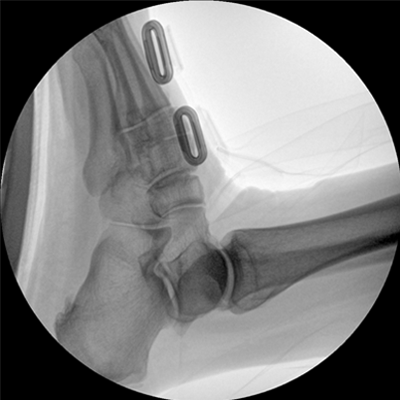

專(zhuān)業(yè)的圖像處理系統(tǒng),為您提供高分辨率、高灰階圖像。